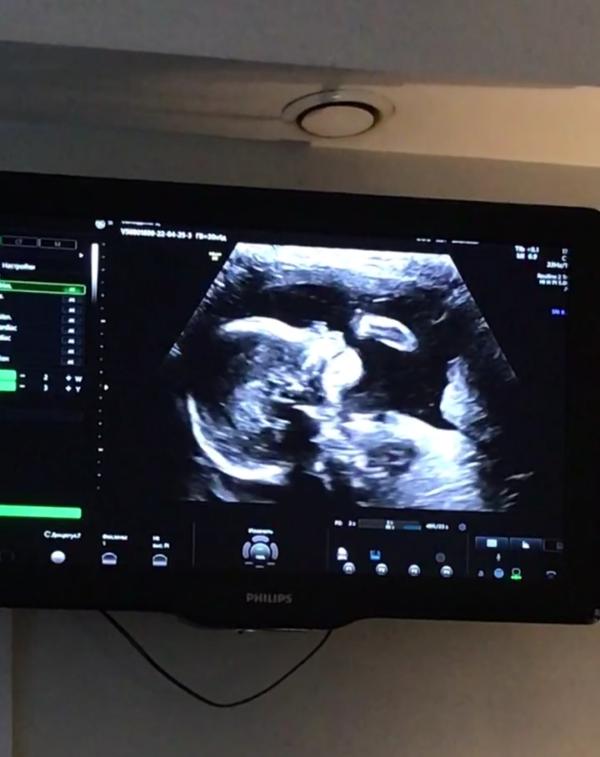

Вот оно наше маленькое счастье,наш малыш❤😍👼

Второй скрининг пройдет,все у нас хорошо🙏🏻 мы почти 400 гр уже😊

Проходила я скриниг в Бионике,врач у меня была Суставова, очень вежливая,на все задаваемые вопросы отвечала,показала все пальчики на ручках и на ножках,сделала нам фотографии,у меня была группа пождержки из двух человек,думала пустят только одного, но нет разрешила всех,как врач понравилась нам😊